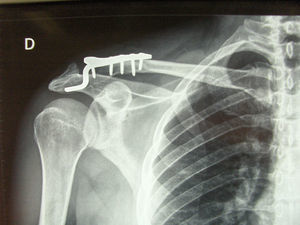

Para el análisis de los resultados se valoró solamente el grupo de las luxaciones agudas de tipo iii al ser más homogéneo y permitir una mejor valoración de los resultados de la técnica (fig. 1). De los 11 casos de la serie, 10 eran hombres y una era mujer. La edad media fue de 38 años (rango de 20–51 años). En 6 casos la lesión se produjo por accidente de tráfico y 5 fueron de etiología laboral (caídas de altura sobre el hombro). Ninguno de ellos presentaba lesiones previas en el hombro intervenido. Diez realizaban una actividad físicamente demandante y uno era sedentario (tabla 1).

El control radiográfico anteroposterior de la articulación AC preoperatorio y postoperatorio (fig. 2) daba suficiente información para valorar pérdidas de reducción de la clavícula, el deterioro de la articulacón AC y la presencia de erosiones subacromiales debidas a la presencia del gancho. La media de retirada de la placa fue a las 9 semanas (rango de 6–12 semanas). El período de seguimiento medio fue de 6 meses (rango de 4–12 meses).